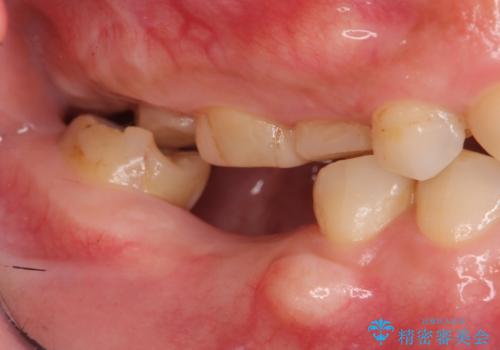

- 欠損し、放置していた奥歯に審美性に優れる入れ歯を作製したいと希望され来院されました。

ノンクラスプデンチャーは、入れ歯に通常ついている目立つ銀色のバネがないため審美性に優れる入れ歯です。

ノンクラスプデンチャーは、ブリッジのように隣りの歯を削る必要もなく、インプラントのように手術も必要ない方法です。